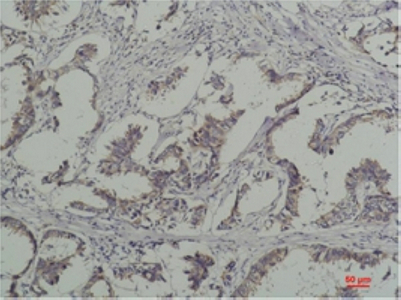

- Immunohistochemistry analysis of paraffin-embedded Human Breast Caricnoma using Phospho-tyrosine antibody.High-pressure and temperature Sodium Citrate pH 6.0 was used for antigen retrieval.